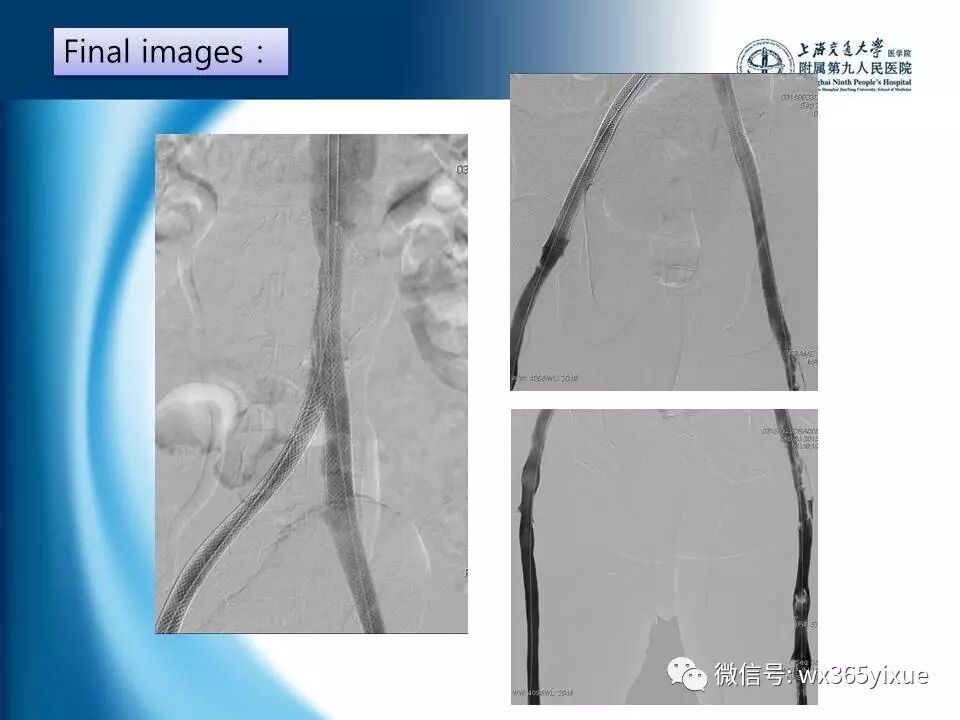

【热点课件】陆信武:滤器相关下腔静脉血栓成的腔内治疗

上海交通大学医学院附属第九人民医院